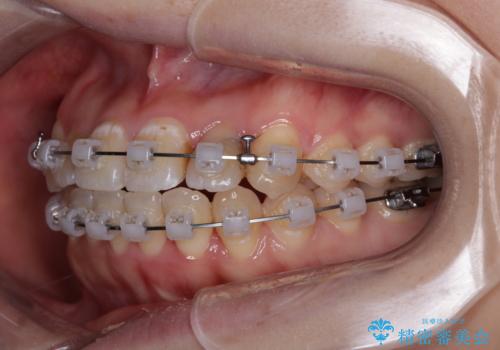

- クリアブラケット

急速拡大装置により上顎骨幅を側方に拡大し、それを利用して八重歯を歯列に納めることにしました。

急速拡大が奏効し、非抜歯矯正にて八重歯を解決することができました。

矯正治療後半で結婚式を挙げられたそうですが、参列された方々からは綺麗に整った前歯に大変驚かれたそうで、非常に満足されていらっしゃいました。